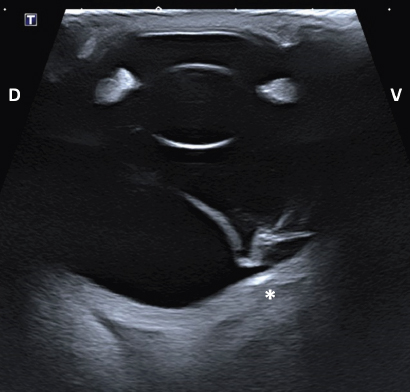

Fig. 4. Transpalpebral ultrasonographic image OS of case 1 in a vertical longitudinal axis. A “seagull sign” is visible in the vitreous, consistent with RD. * Note the depression at the caudoventral aspect of the globe, in the area of the optic disk (not visible on this isolated image). D: dorsal; V: ventral.

Intraocular lesions found on US and MRI of both horses were consistent with the ophthalmic examination. Complete RD OS and hyperechoic vitreous floaters OU were noted on US (Fig. 4). RD was also evident OS on MRI, more conspicuously on T2W and FLAIR sequences. In T2 sequences, the detached retina was identified as a V-shaped membrane of intermediate signal inside the hyperintense vitreous and reaching the optic disk (Fig. 5A), while it was slightly hyperintense in comparison to the hypointense vitreous chamber on FLAIR acquisitions (Fig. 5B). There was a subjectively abnormal positioned optic disk OU on US and MRI, suggesting ectopic ONH. OS was flattened at the level of the ONH in both horses. Except for a subarachnoid emphysema due to postmortem changes, the brain looked otherwise normal on MRI. Based on US, the axial globe length measured 39.2 mm OS and 41.5 mm OD of case 1 and 45 mm OU in case 2.